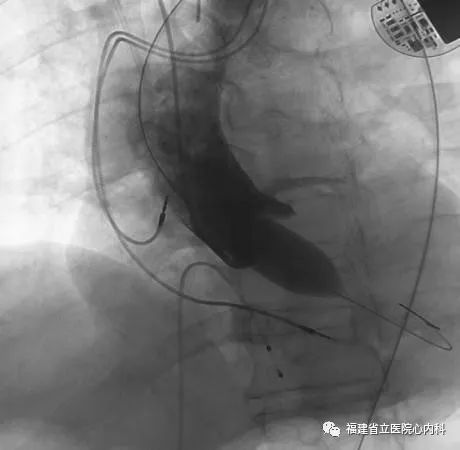

病例3

该病例是一个单纯重度主动脉瓣返流患者,主动脉瓣上没有稳定的锚定结构,通过依靠瓣环及左室流出道,瓣膜移位及瓣周漏风险大,手术难度极大,术者通过CT仔细制定了手术策略及各种预案,最终顺利植入29号瓣膜,术后无返流及瓣周漏,手术效果佳。

瓣环

窦部

植入L29瓣膜